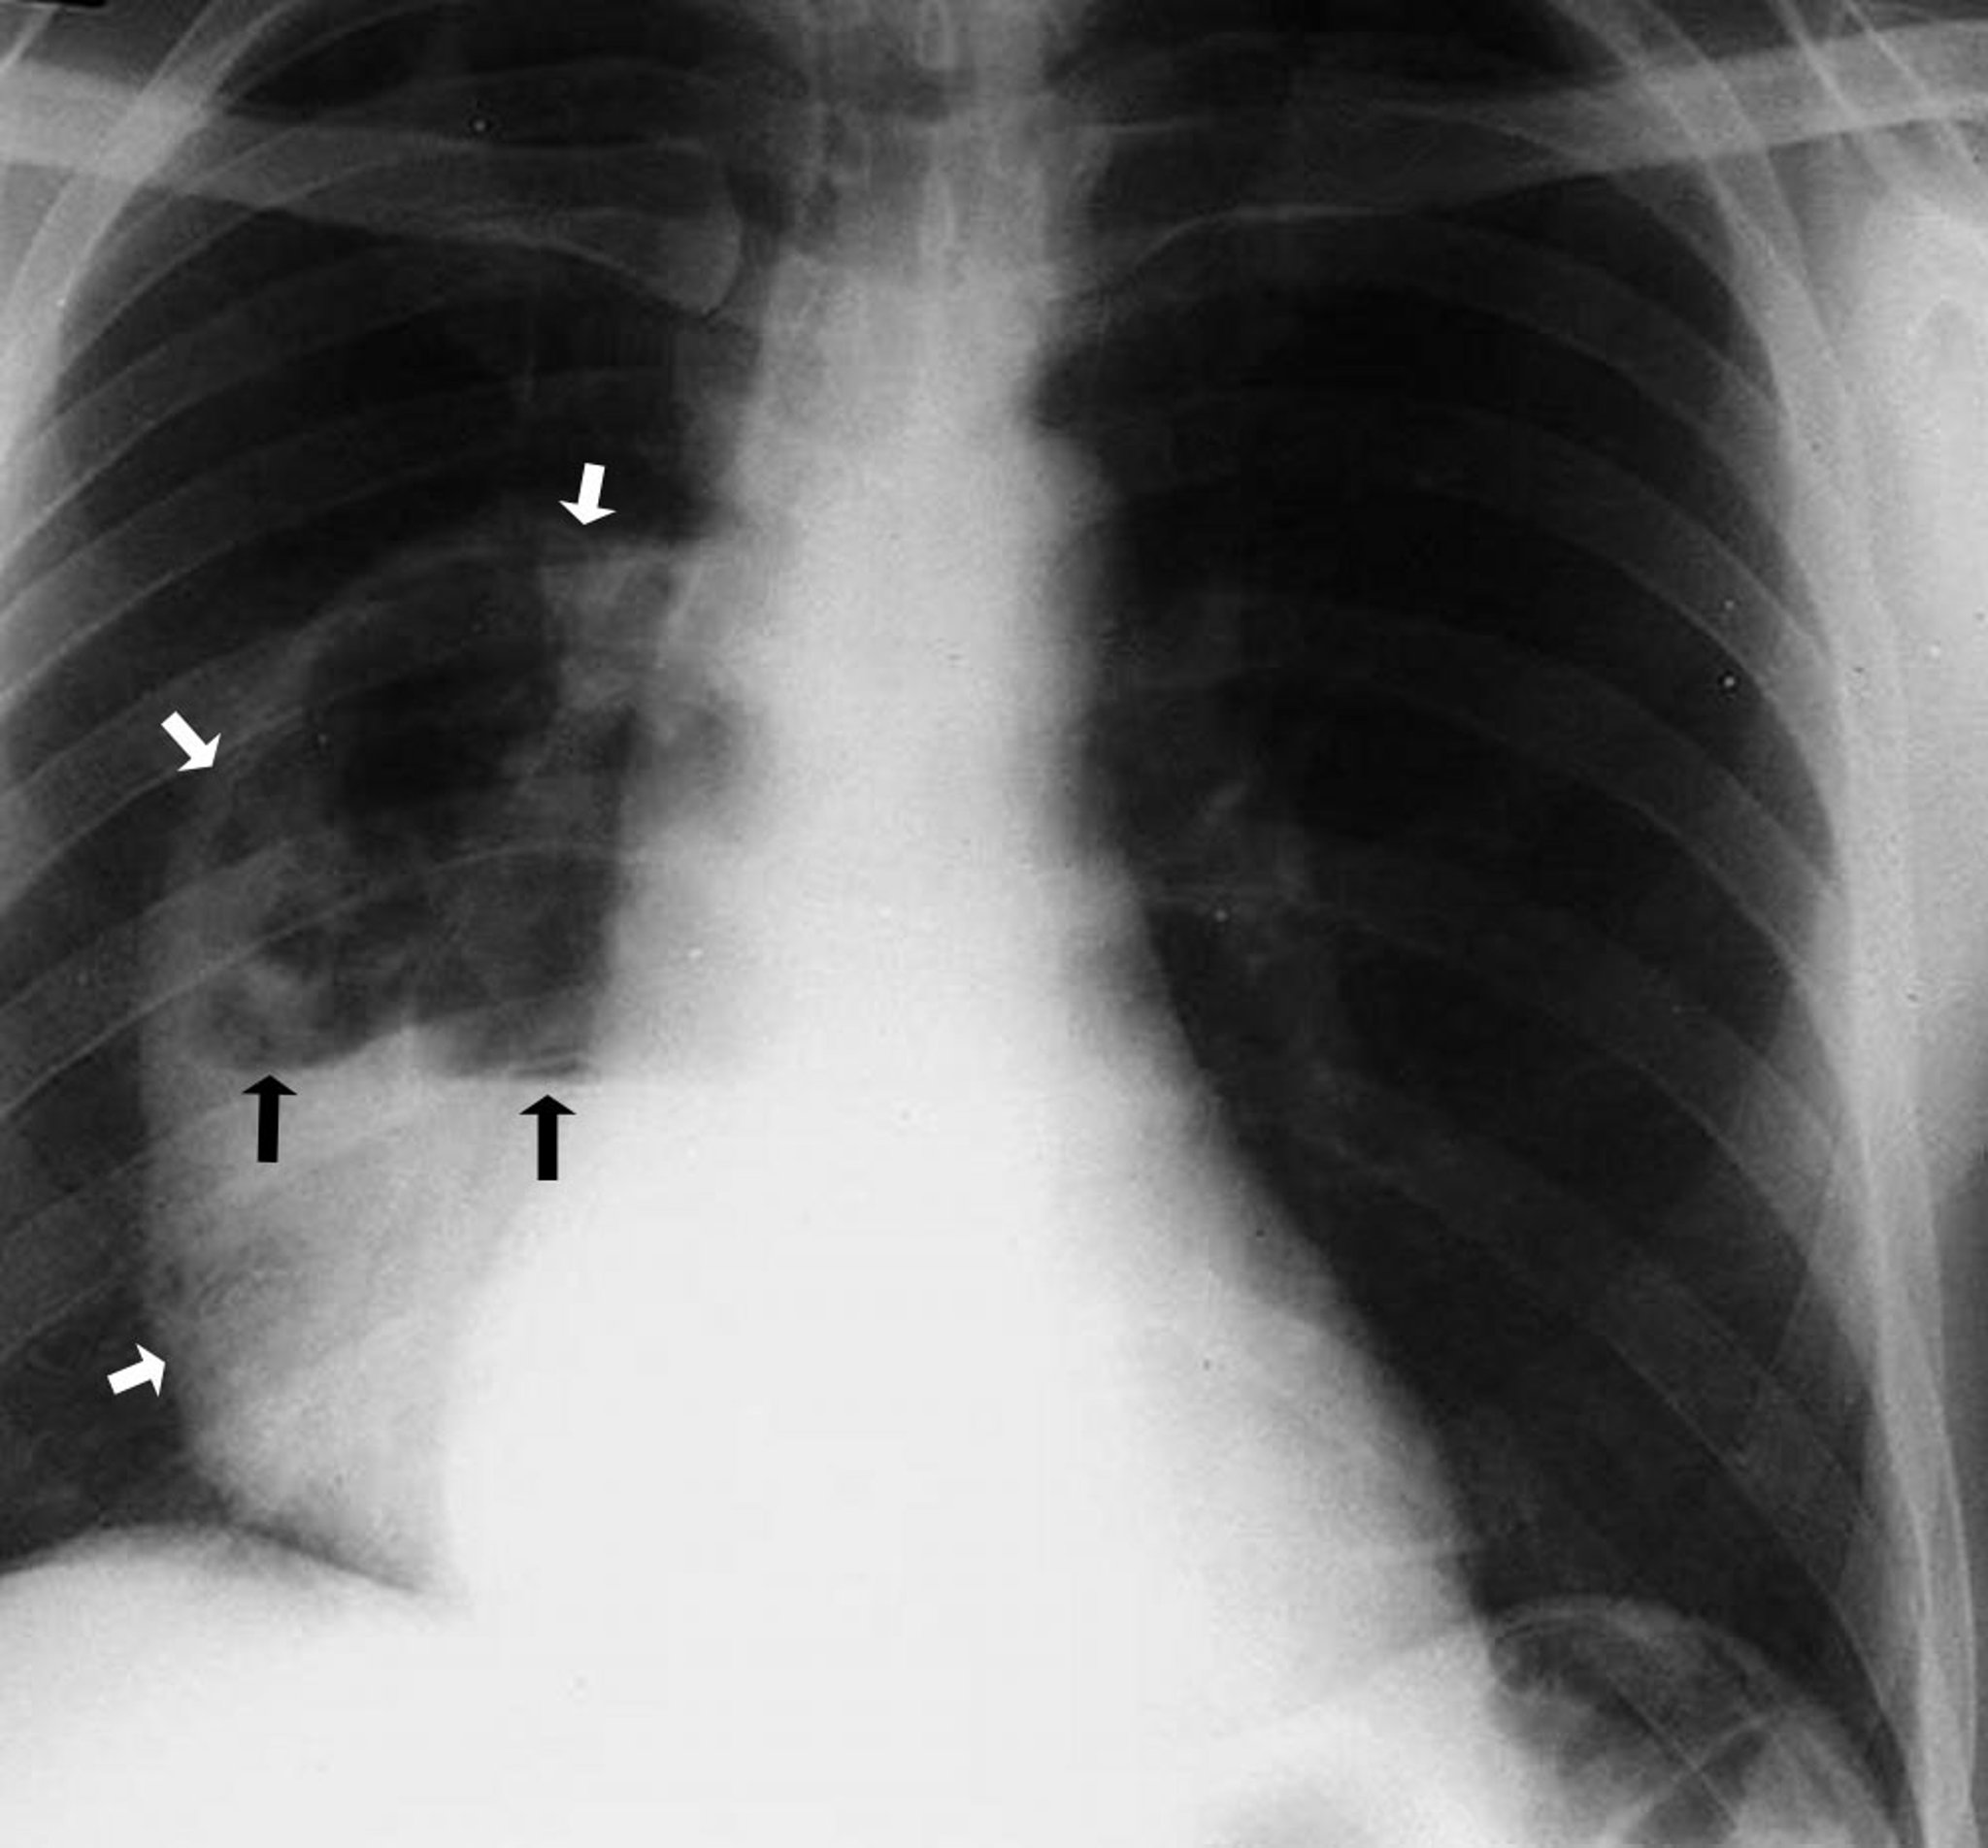

Absceso pulmonar (radiografía)

Esta foto muestra un absceso de gran tamaño en el lóbulo inferior derecho con una cavidad que contiene un nivel hidroaéreo. Las flechas blancas señalan el límite del absceso mostrando las paredes separadas del parénquima pulmonar. Las flechas negras señalan el nivel donde se encuentran el aire arriba y el líquido abajo.

By permission of the publisher. De Leaf H. In Atlas of Infectious Diseases: Pleuropulmonary and Bronchial Infections. Publicado por GL Mandell (series editor) y MS Simberkoff. Philadelphia, Current Medicine, 1996.